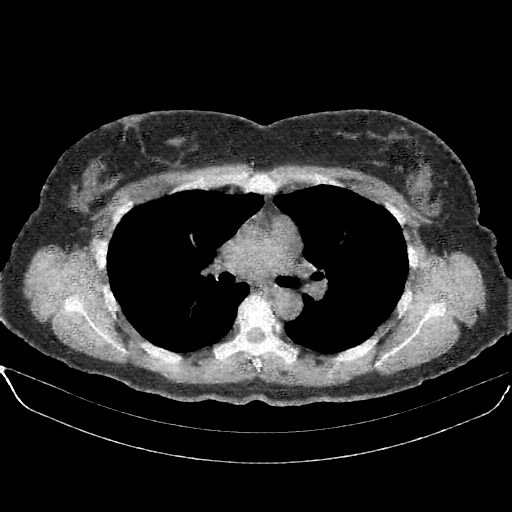

Original VENOUS CT scan

Full window (WL 1023.5, WW 4095 β†’ Low βˆ’1024, High +3071)

Lung window (WL -600, WW 1500 β†’ Low βˆ’1350, High +150)

Mediastinum window (WL 40, WW 400 β†’ Low βˆ’160, High +240)